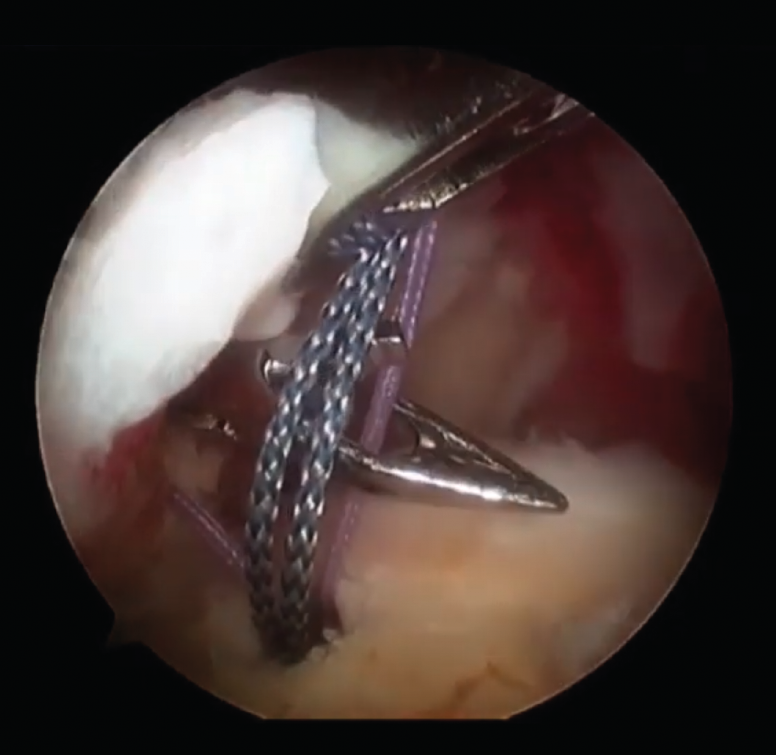

¿El resto de los procedimientos planteados son eficientes? El objetivo es obtener un hombro indoloro para una buena rehabilitación, con lo que la fisioterapia posterior al procedimiento quirúrgico tendrá un papel fundamental en la capacidad de recuperación del hombro (Figura 3).

Figura 3. Revisión de una rotura de manguito rotador.